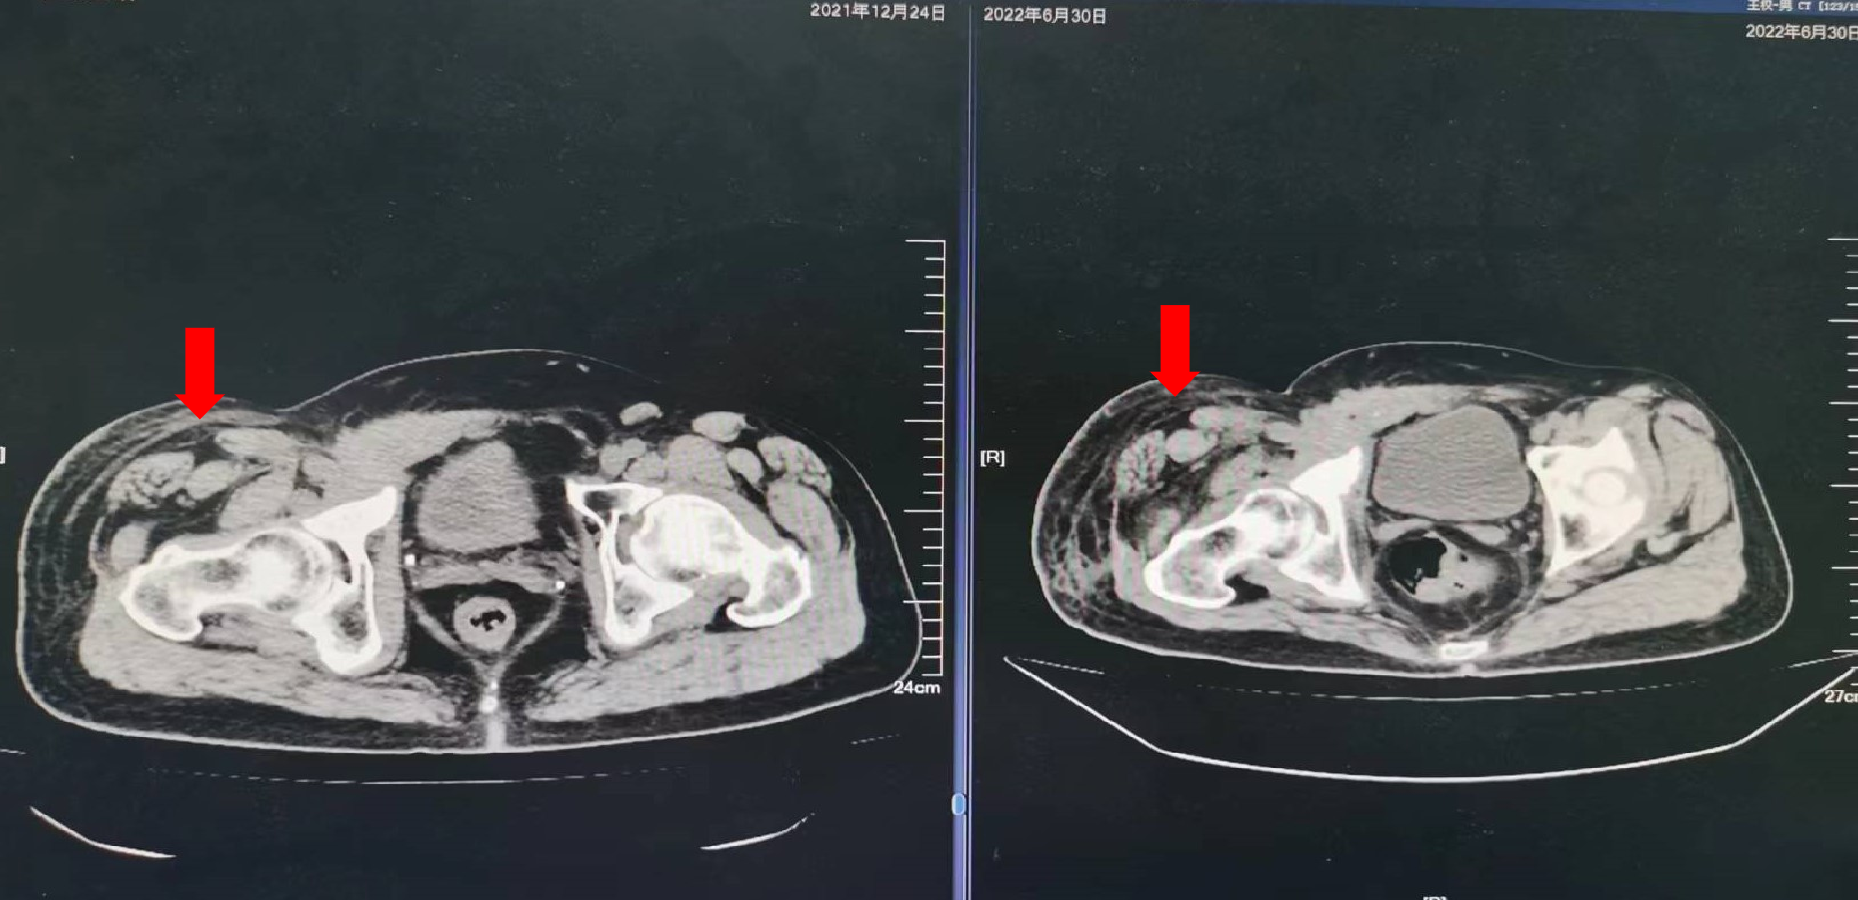

2018年6月:复查腹部CT示:右腹股沟淋巴结肿大;穿刺活检:转移性腺癌,符合结肠来源。

2018年10月29日:复查腹部CT:前腹壁下部可见不规则软组织密度肿块,范围约4.8cm*4.2cm,与后方髂外动静脉分界不清。开始行XELOX方案化疗6周期(奥沙利铂200mg d1+卡培他滨1500mg每日2次*14)。

2021年1月6日:于辽宁中医药大学附属医院肿瘤科住院,右腹股沟肿胀疼痛明显,行动受限,复查彩超提示右侧股浅及腘静脉血栓形成(右侧股总、大隐静脉无法探及),予强阿片类药物止痛及利伐沙班口服抗凝治疗。

2021年5月27日:开始口服曲氟尿苷替匹嘧啶片(TAS-102)55mg每日2次 d1-5,d8-12,Q4W配合信迪利单抗免疫治疗。

疗效评价:SD,患者右腹股沟肿胀疼痛明显减轻,停用止痛药,PFS时间为10个月,主要不良反应为Ⅱ度骨髓抑制。